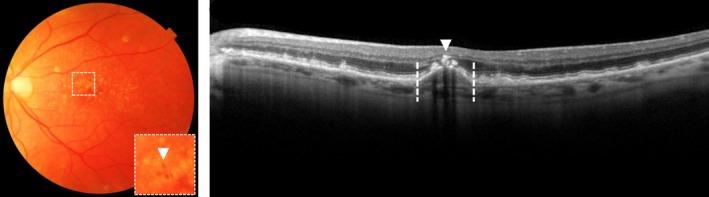

Age-related macular degeneration (AMD) is a degenerative disease of the macula, often leading to progressive vision loss. The rate of disease progression can vary among individuals and has been associated with multiple risk factors. In this review, we provide an overview of the current literature investigating phenotypic, demographic, environmental, genetic, and molecular risk factors, and propose the most consistently identified risk factors for disease progression in AMD based on these studies. Finally, we describe the potential use of these risk factors for personalised healthcare.

While phenotypic risk factors such as drusen and pigment abnormalities become more important to predict disease progression during the course of the disease, demographic, environmental, genetic and molecular risk factors are more valuable at earlier disease stages. Demographic and environmental risk factors such as age and smoking are consistently reported to be related to disease progression, while other factors such as sex, body mass index (BMI) and education are less often associated. Of all known AMD variants, variants that are most consistently reported with disease progression are rs10922109 and rs570618 in CFH, rs116503776 in C2/CFB/SKIV2L, rs3750846 in ARMS2/HTRA1 and rs2230199 in C3. However, it seems likely that other AMD variants also contribute to disease progression but to a lesser extent. Rare variants have probably a large effect on disease progression in highly affected families. Furthermore, current prediction models do not include molecular risk factors, while these factors can be measured accurately in the blood. Possible promising molecular risk factors are High-Density Lipoprotein Cholesterol (HDL-C), Docosahexaenoic acid (DHA), eicosapentaenoic acid (EPA), zeaxanthin and lutein.